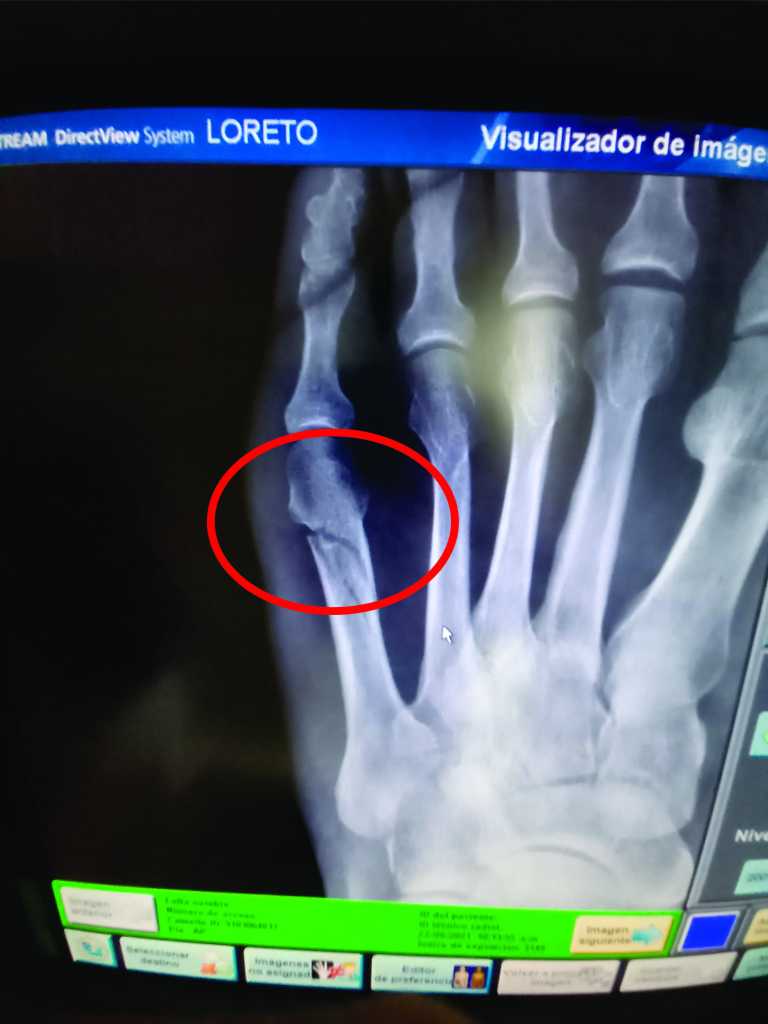

That evening, we went with Charlie and LeeAnne to the resort for supper and had the usual good food and pleasant time. However, on getting back in the boat after dinner, I stepped awkwardly into the cockpit and rolled over on my foot. Although I suspected it was more than a usual sprain, it was to be a few days until it was confirmed that I had indeed broken a bone in my foot.

THE FOOT: The Wednesday after arriving, with no improvement to the foot, and having rented a car for us and Juliet to go to Loreto, we stopped by the hospital. A very short visit, 600 pesos and a diagnosis by the radiography tech and a security guard, and I was on my way with a photo of an x-ray on my phone.

The result … A big boot … not the best for dinghy boardings or moving around the boat, but better than a cast.